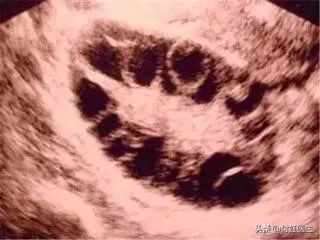

玉鍍的盆腔超聲提示:雙側(cè)卵巢可見(jiàn)十余個(gè)無(wú)回聲,右側(cè)較大者直徑約0.9cm,左側(cè)較大者直徑約0.5cm,她診斷“多囊卵巢綜合征”嗎?

美國(guó)內(nèi)分泌學(xué)會(huì)( The Endocrine Society)2013 年 PCOS 的診療指南,即符合以下 3 條中的 2 條,并排除其他疾病導(dǎo)致的類似臨床表現(xiàn),即可診斷 PCOS:(1)雄激素過(guò)多的臨床和(或)生化表現(xiàn),如多毛,痤瘡,雄激素性脫發(fā),血清總睪酮或游離睪酮升高;(2)稀發(fā)排卵或無(wú)排卵;(3)卵巢多囊樣改變,即單側(cè)卵巢體積增大超過(guò) 10ml(排除囊腫及優(yōu)勢(shì)卵泡)或單側(cè)卵巢內(nèi)有超過(guò) 12 個(gè)的直徑 2~9mm 卵泡。

我國(guó)的 PCOS 診斷標(biāo)準(zhǔn)中,月經(jīng)稀發(fā)或閉經(jīng)或不規(guī)則子宮出血是診斷的必需條件。另外,再符合下列 2 項(xiàng)中的一項(xiàng),并排除其他可能引起高雄激素的疾病和引起排卵異常的疾病后,可診斷為 PCOS:(1)高雄激素的臨床表現(xiàn)或高雄激素血癥;(2)超聲表現(xiàn)為多囊卵巢。